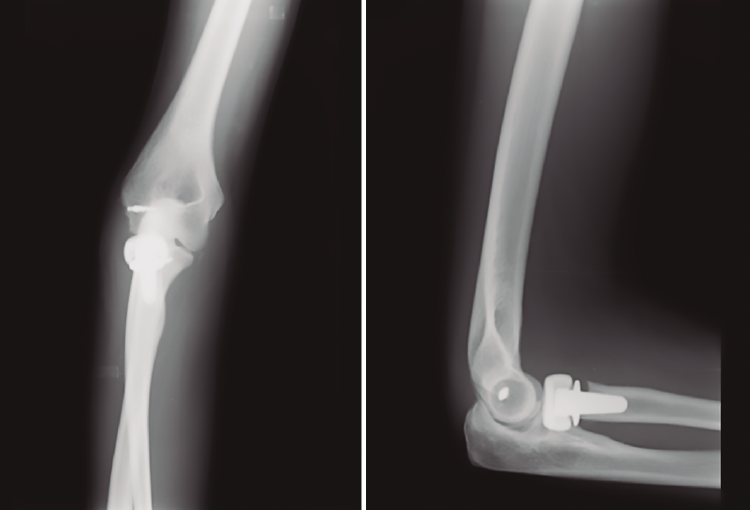

Figura 1. Radiografía inicial realizada el 26/08/2017.

Sufre un accidente laboral in itinere yendo en bicicleta el 28/08/2017. Acude al Servicio de Urgencias, siendo diagnosticada de Fx luxación de codo derecho y, tras estudio radiológico (Figura 1), se decide intervención quirúrgica.